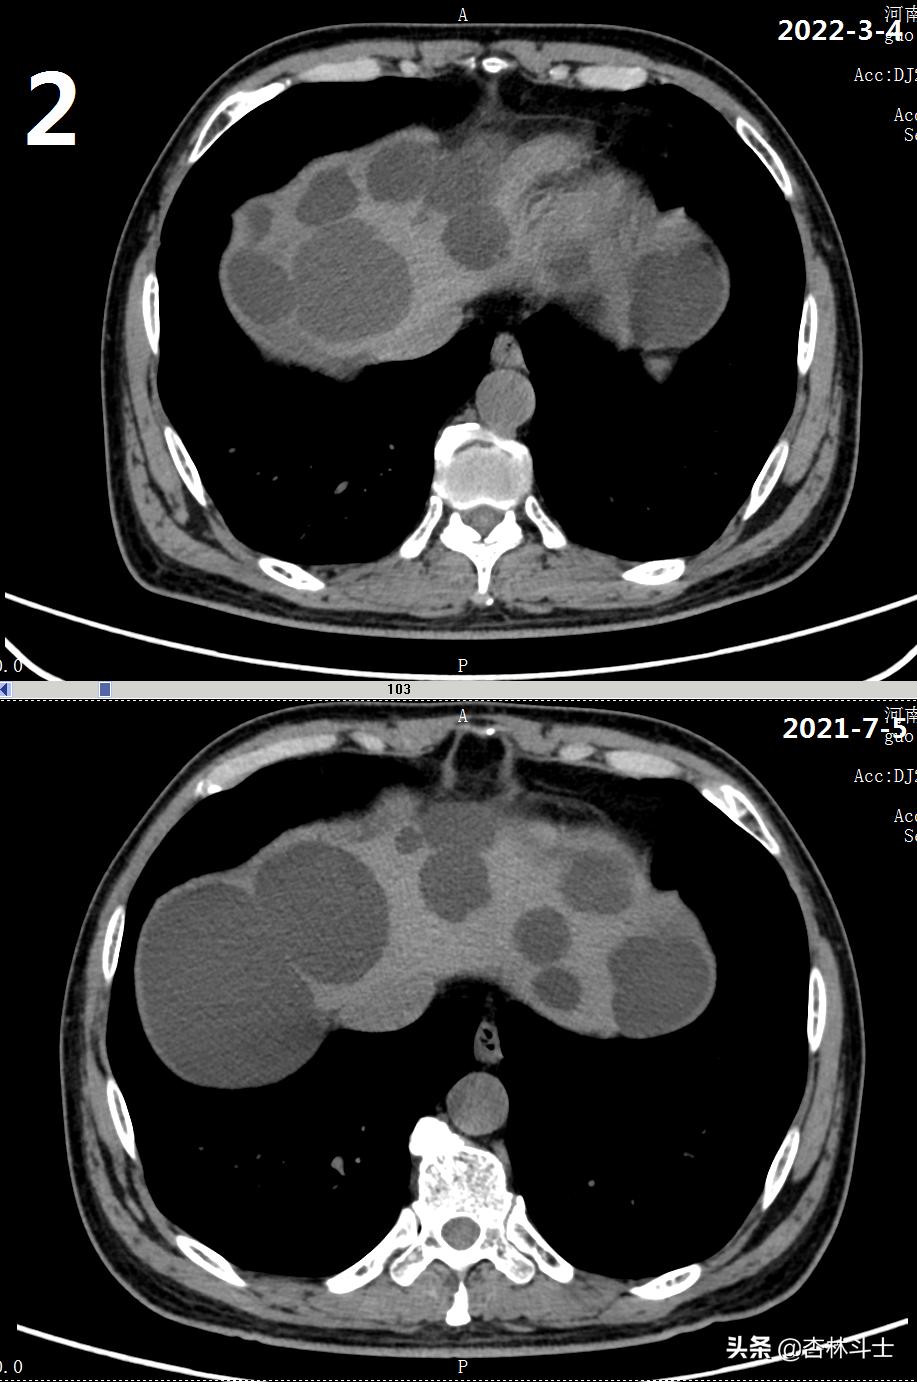

64岁退休银行职员,腹胀5年,加重2月,第二次入住我院消化内科。下图1-6为本次复查上腹部CT与2021-7-5肝囊肿经皮肝穿刺抽吸无水酒精硬化术前的对比图。

可明显看出,肝内囊肿较前减少,肝实质所占体积明显增加。